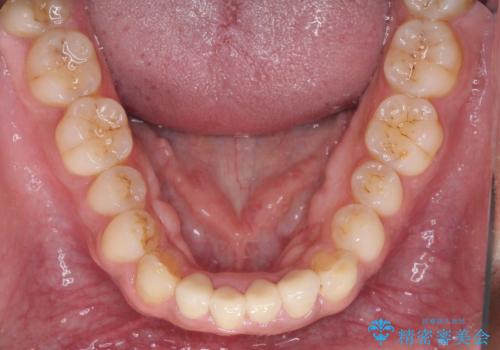

- 下の前歯がすり減って、痛みがあるとのことで来院された患者様です。

咬合力が強く、4本のうち3本の歯が失活しており、腫れや痛みが認められました。

3歯に根管治療を行い、その後4歯をオールセラミッククラウンにて補綴することとしました。

根管治療により腫れと痛みが引き、叢生の認められた歯列は補綴治療により改善され、清掃性が増しました。